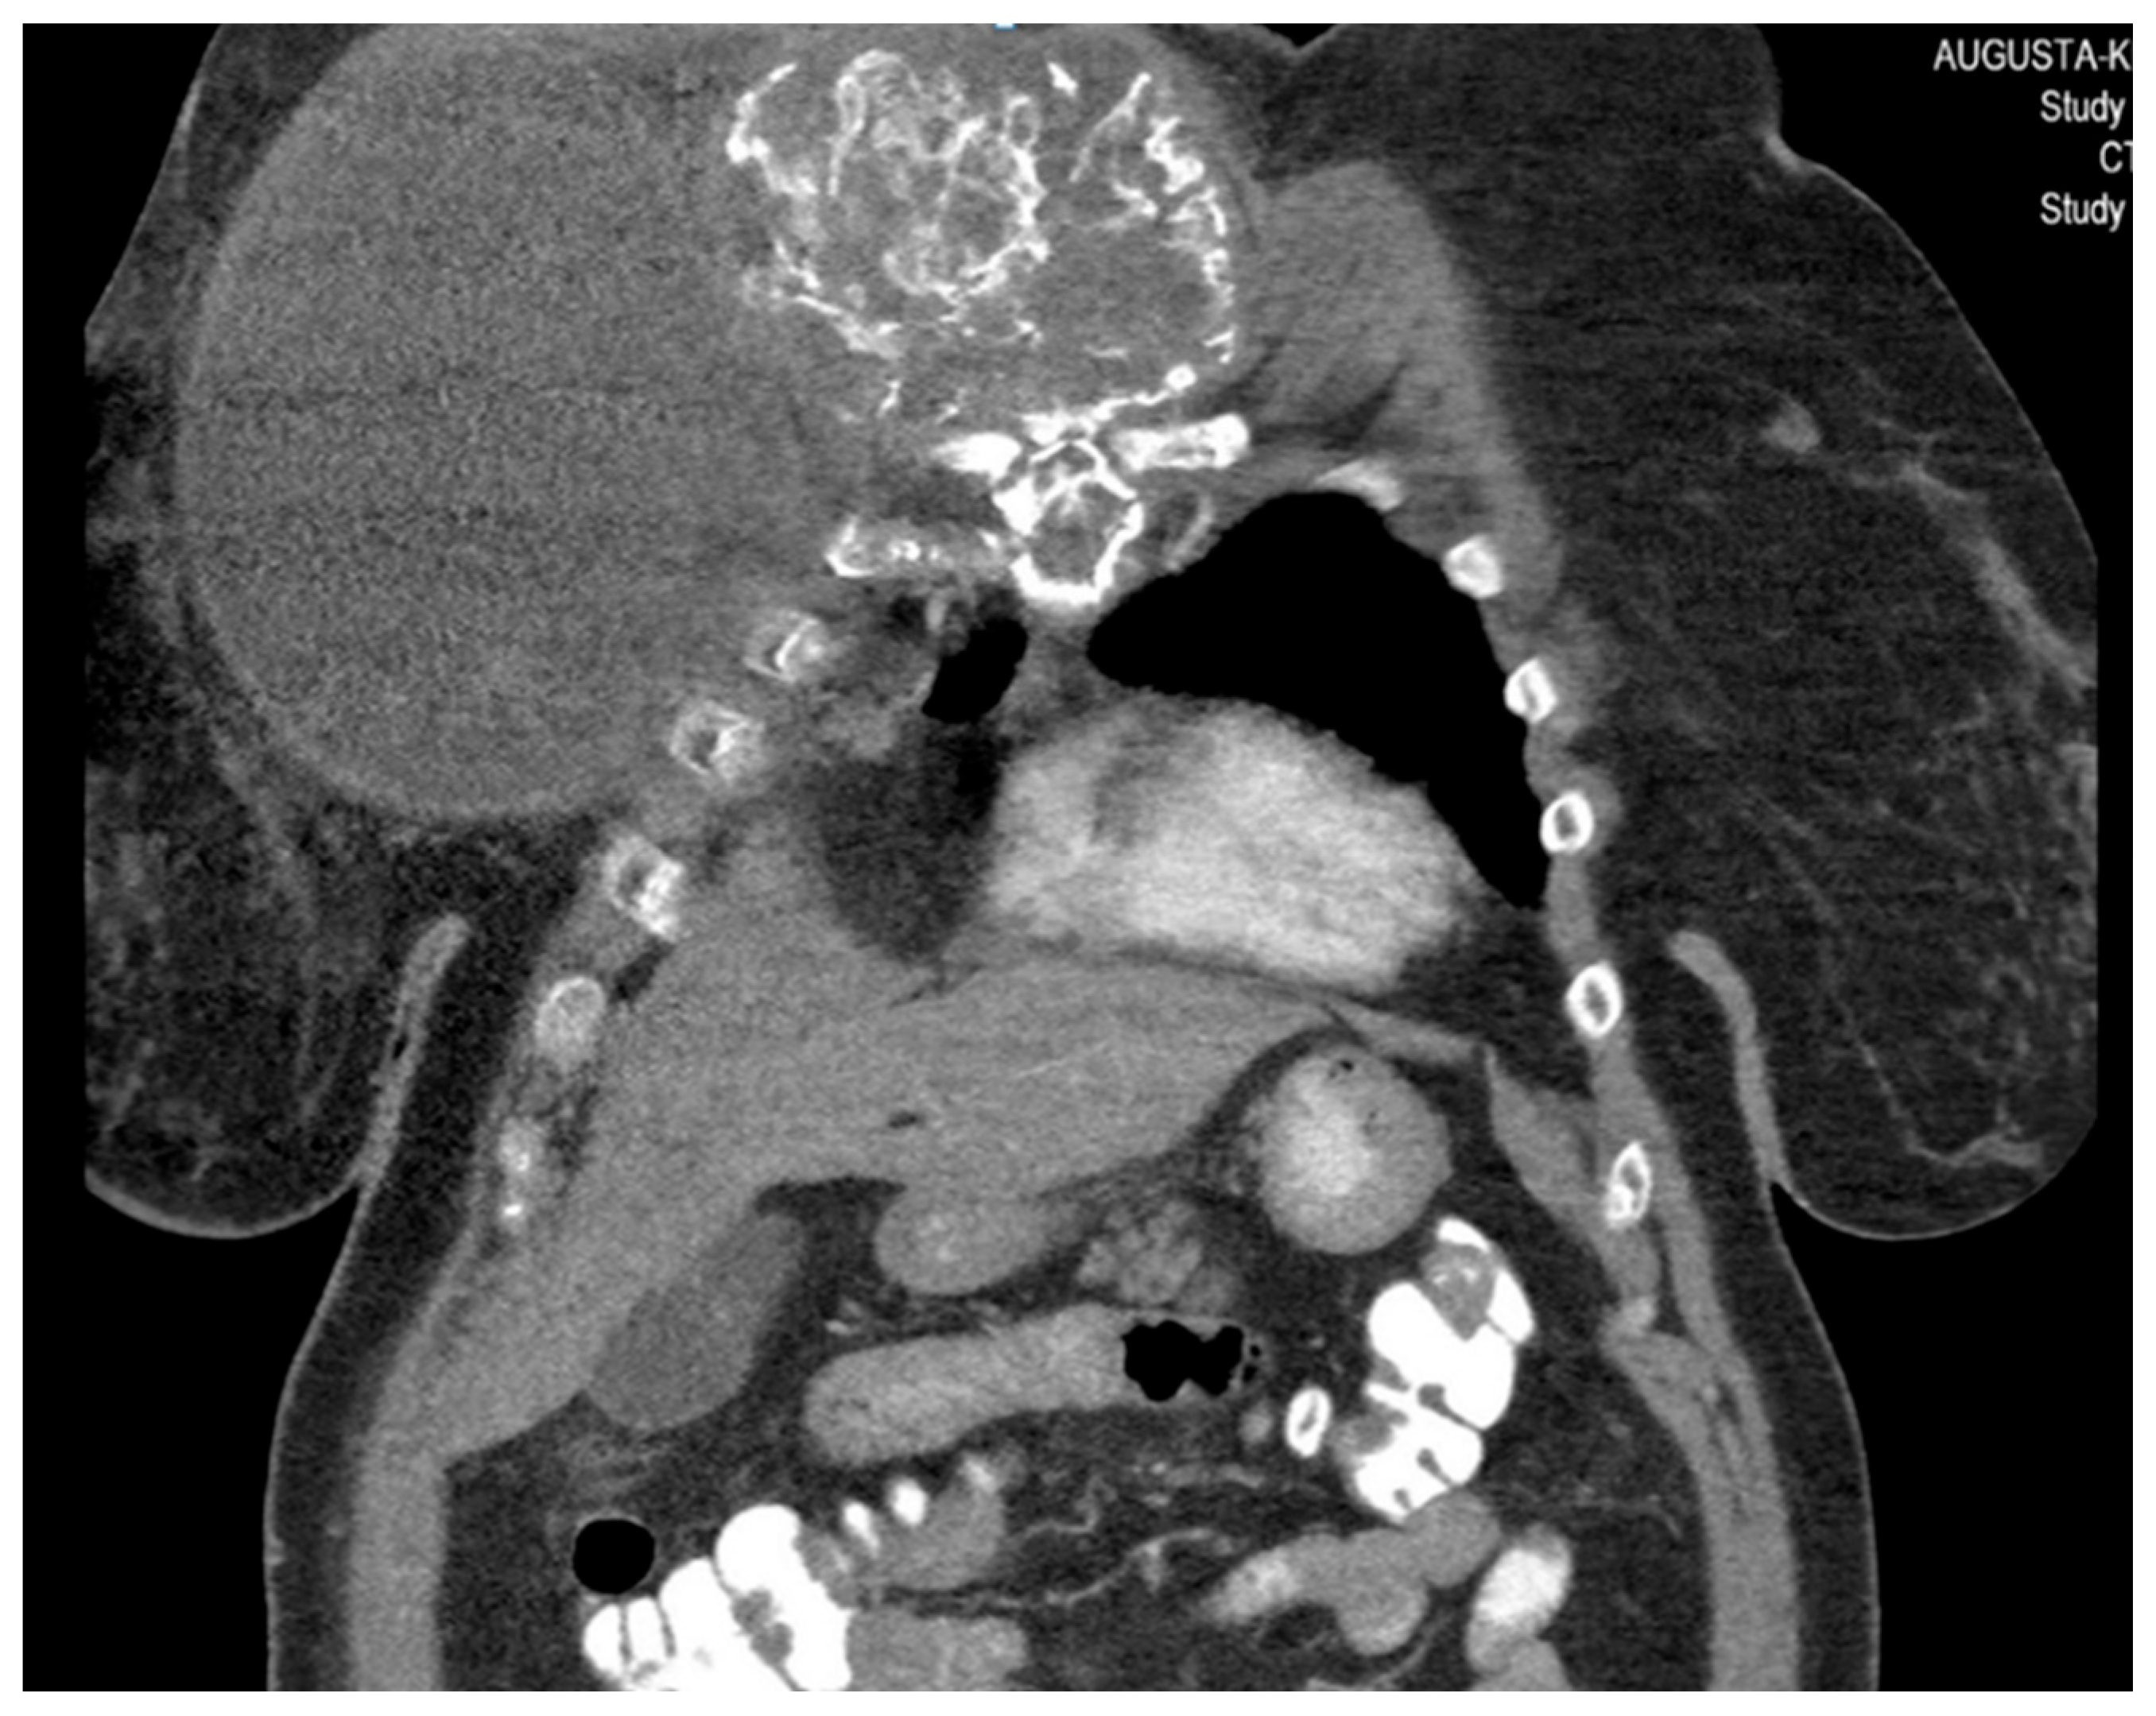

She returned to Bochum in June 2018 with the following symptoms: on the right ventral chest wall, she had a large tumor with a perforation in the pericardium of approximately 15 × 20 cm, an abdominal inguinal tumor on the right, and an ulcerating tumor on the lower left side of the abdomen. A computed tomography of the thorax and abdomen was performed in 09/2018 (Figure 2 and Figure 3) and a magnetic resonance imaging of the thorax was performed in 06/2018 (Figure 4 and Figure 5).

Figure 3.

Computed tomography of the thorax and abdomen (CT Thx/Abd) in 2018. There is a large, partially calcified soft tissue structure of the right breast with central hypodensity and possibly mucinous parts. The image shows infiltration of the thoracic wall and transfer to the mediastinum, with destruction of the corpus and manubrium sterni and infiltration of the musculus pecotralis major and the musculus serratus anterior on the right. Additionally, destruction of the adjacent medial clavicle on the right and of the first rib medial on the right was observed. The formation directly infiltrates the mediastinum, with infiltration of the pericardium and direct contact with the aortic arch. The maximum extent of this conglomerate was 25.2 × 14.8 × 10.0 cm (VU 22.7 × 16.6 cm axial; not fully recorded cranially). There was no flow obstruction of the right-side vessels of the upper thoracic aperture.